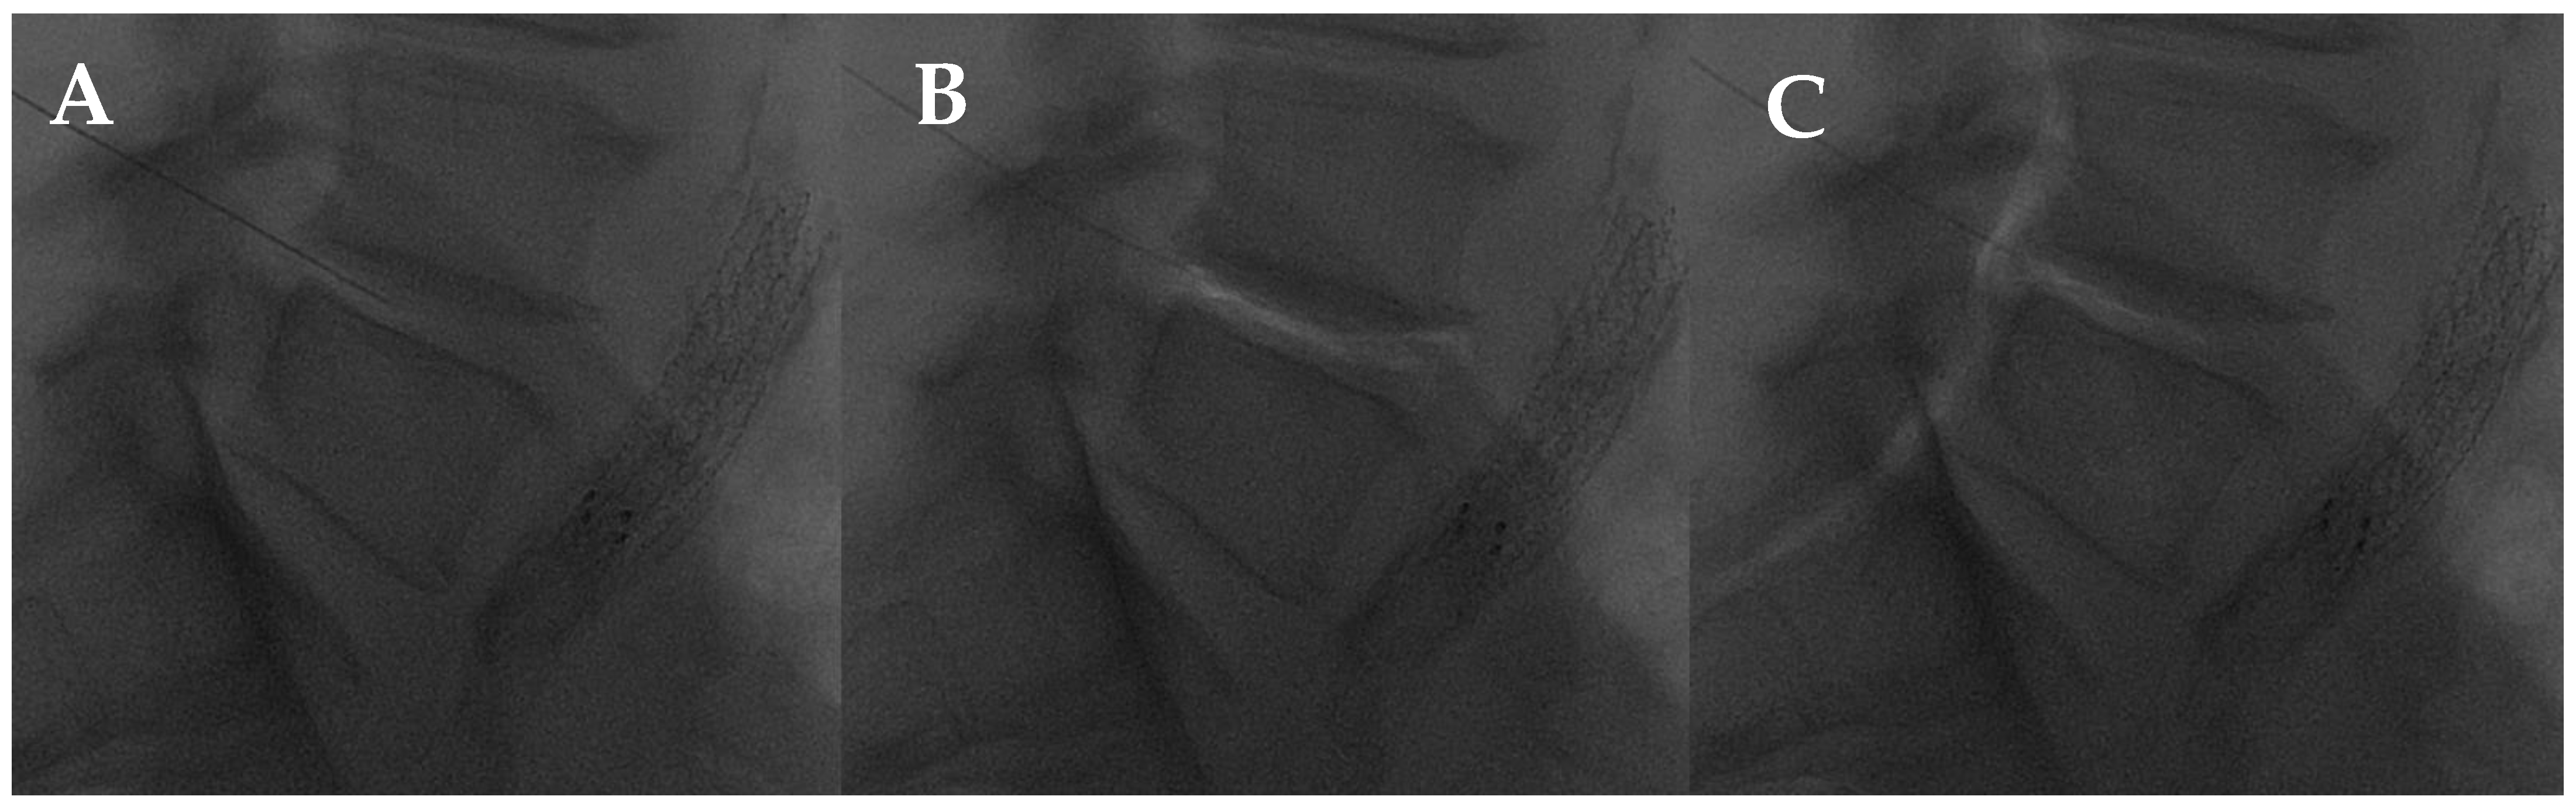

Essentially, percutaneous O2-O3 treatment is the main application for musculoskeletal disorders, such as arthritis, tendonitis, or other diseases, including chronic LBP [102]. The mechanisms of action of the intradiscal, facet joint, and periganglionic O2-O3 injection have been explored in many studies. In the interaction with water and polyunsaturated fatty acids, O2-O3 generates reactive oxygen species (ROS), which results in the cascade of antioxidant response elements and the subsequent downregulation of the inflammatory response. Several enzymes are involved in this process, including nuclear factor-erythroid 2-related factor 2 (NRF2), a key element for antioxidant human mechanisms [101,103,104]. The capacity of the nucleus pulposus to hold water may be compromised by the O2-O3 oxidizing activity, which may disrupt glycosaminoglycan chains and dehydrate the nucleus pulposus. The O2-O3 chemodiscolysis would reduce the size of the hernia and eliminate hernial conflict (Figure 8), despite not being able to alter the natural course of the disc degeneration process and endplate changes (Modic changes) [105,106,107].

Figure 8.

L4-L5 intradiscal oxygen–ozone chemonucleolysis. (A) Intradiscal puncture on lateral view; (B) intradiscal; and (C) intraforaminal oxygen–ozone mixture injection.